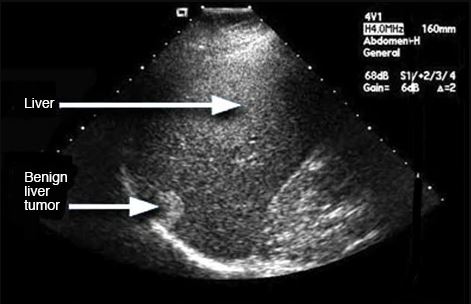

An ultrasound scan uses high-frequency sound waves to create images of the inside of the body. It is suitable for use during pregnancy. Ultrasound scans, or sonography, are safe because they use sound waves or echoes to make an image, instead of radiation.

The images can provide valuable information for diagnosing and treating a variety of diseases and conditions.

An ultrasound helps doctors look for tumors in certain areas of the body that don’t show up well on x-rays. Doctors often use them to guide a needle during a biopsy. Ultrasounds are usually quick and most don’t require special preparation.